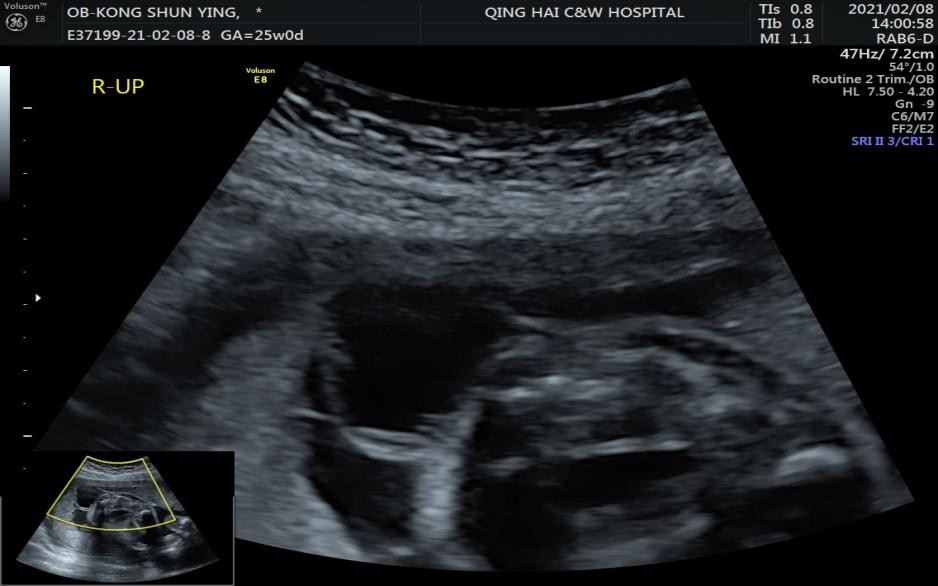

我院作为青海省出生缺陷综合防治管理中心,目前我院产科三级筛查(就是常说的四维彩超)及胎儿超声心动图现在已步入常态化产前检查,随着检查人数的增加,筛查的阳性人数也在攀升。

据统计,青海省妇幼保健院超声科自1-3月份检出异常复杂病例共45例,包括心脏畸形共有18例(其中胎儿心脏畸形有13例,小儿心脏畸形有5例),其他胎儿畸形方面共有9例,妇科方面有13例,浅表器官5例。

XXX 女 23岁 双胎 早孕期规律服用叶酸,检查产科三级筛查时发现双胎之一有脊柱裂(脊髓脊膜膨出并脊髓栓系)